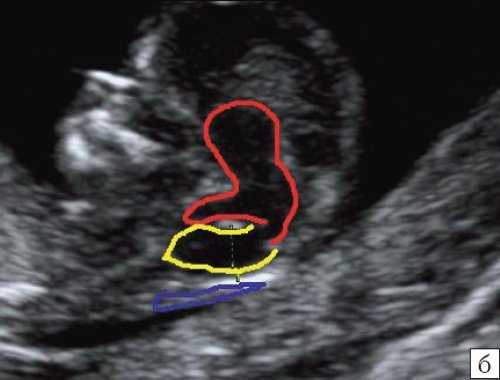

При частичном РЭС в наблюдении 4 картины желудочковой системы (затылочные рога боковых желудочков - 7 и 7,9 мм, 3-й желудочек - до 2 мм), комплекса "полость прозрачной перегородки (ППП - 3,4 мм) - мозолистое тело (20,8 мм)", борозд мозга (глубина сильвиевой борозды - 7 мм), длины крыши четверохолмия (8,3 мм), водопровода, передне-задних диаметров мезенцефалона (11 мм) и моста (7,9 мм) соответствовали норме (рис. 6).

На эхограмме: М - мозжечок, Ц - цистерна, стрелка короткая - намет мозжечка, стрелка длинная - 4-й желудочек.